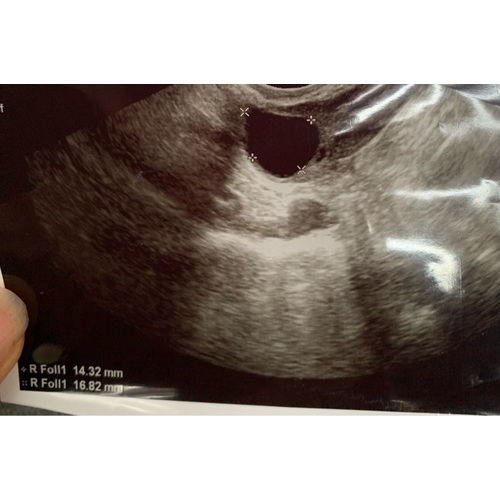

Een follikel kan vanaf 15 Mm mee doen met een eisprong. Wanneer je hormoonstimulatie gebruikt zoals Clomid kunnen ze doorgroeien tot 26 Mm tot de eisprong.. ovulatietesten geven een indicatie om de eisprong te bepalen. Ik raad je aan om deze te gebruiken.

Ik gebruik geen medicatie .. ze meten me wel ik moet woensdag terug ze zei ik denk dn dat hij wel gesprongen is. Ik ben bang dat ik niet optijd had geklust

Ik heb hier ook een vraag over. Ik had vorige week maandag een follikel van 18 mm. Nu heb ik vandaag (7 dagen later) bloed laten prikken en heb ik schijnbaar nog geen eisprong gehad. Hoe kan dit? (Ik heb 3 dubbele dosis letrozol geslikt)